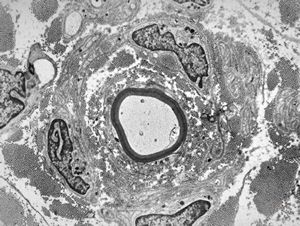

![F,23y. | n.suralis - hypertrophic demyelinating neuropathy [onion bulb] F,23y. | n.suralis - hypertrophic demyelinating neuropathy [onion bulb]](../img/OGDEM/015 Soft tissues/0077.jpg)

F,23y. | n.suralis - hypertrophic demyelinating neuropathy [onion bulb]